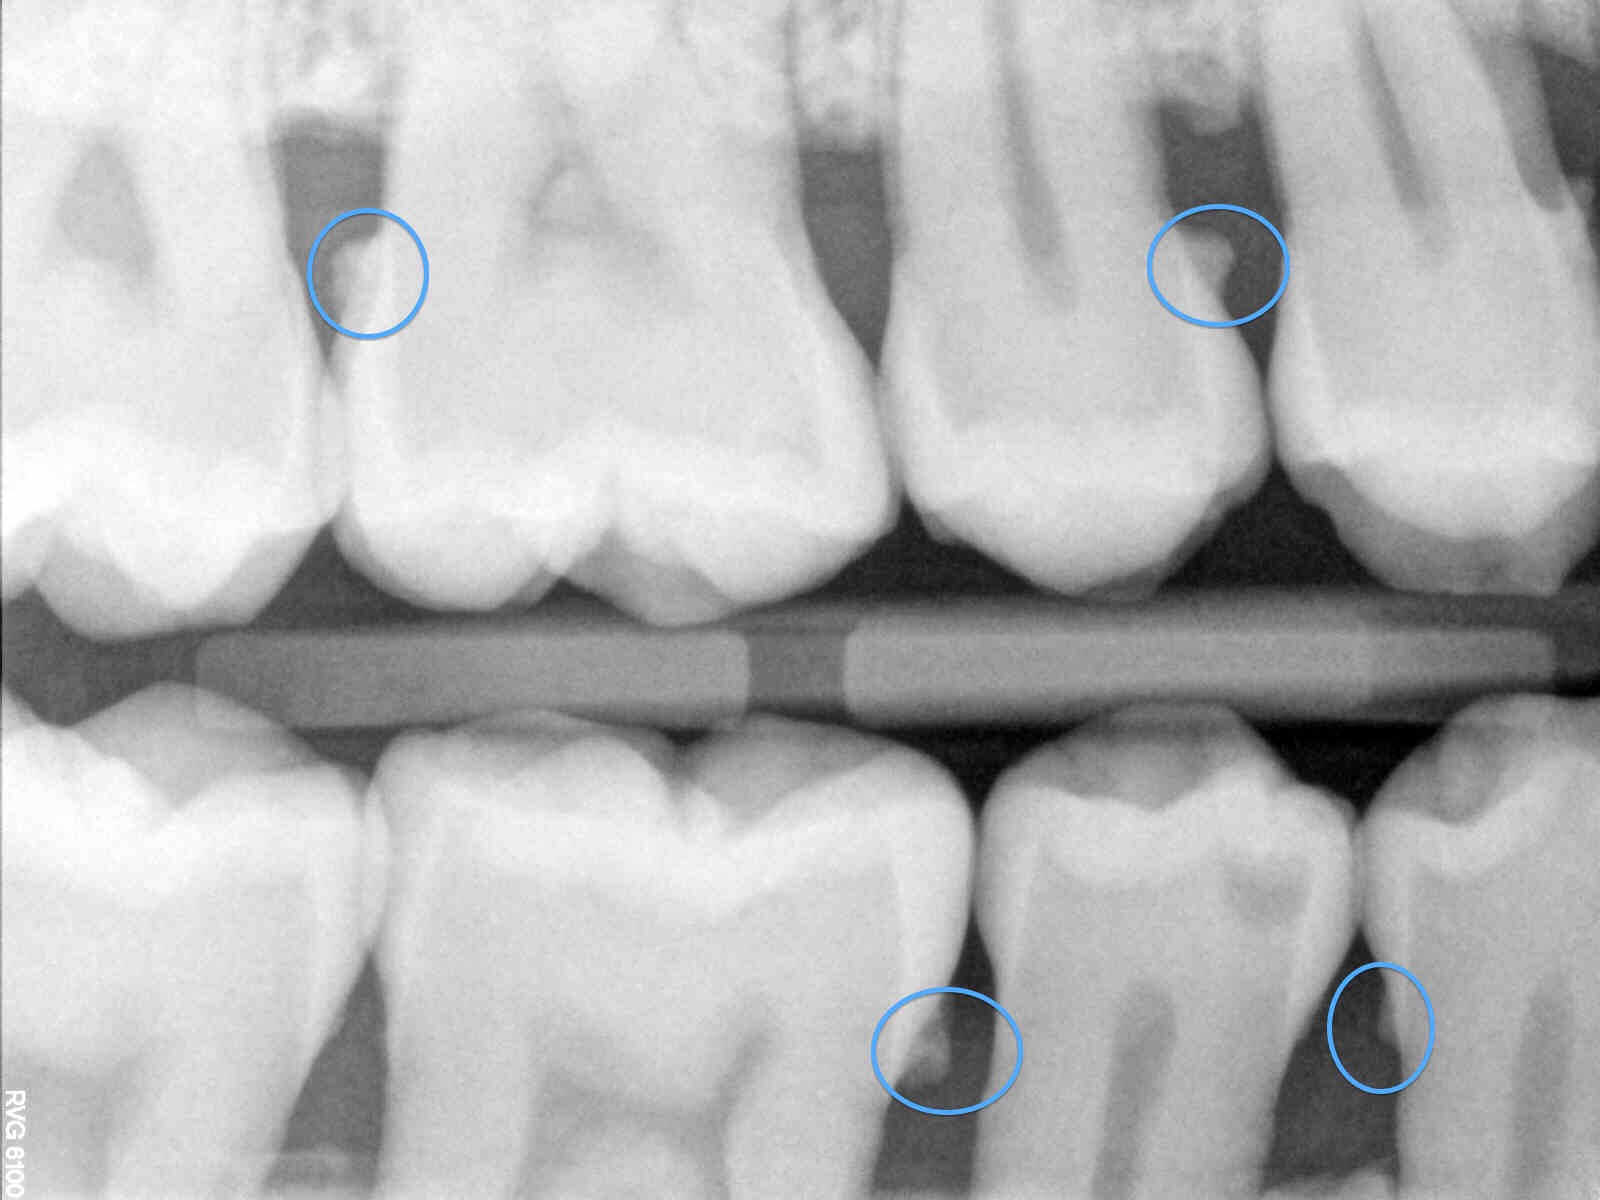

I actually care about the bacteria that is making yuck babies under your gums so I need a sub gingival explorer. Hygienists know that a great brusher can have a myriad of chunky bacteria under their gums. Plaque happens. I honestly believe the underuse of my dear ODU 11/12 is one of the reasons why a patient can move from the dental chair to the hygiene chair and go from a prophy to four quads of scaling and root planing. Patients that brush fairly well can have pretty decent looking gingival tissue at first glance, but what lies beneath are knee cap shaped calculus deposits.